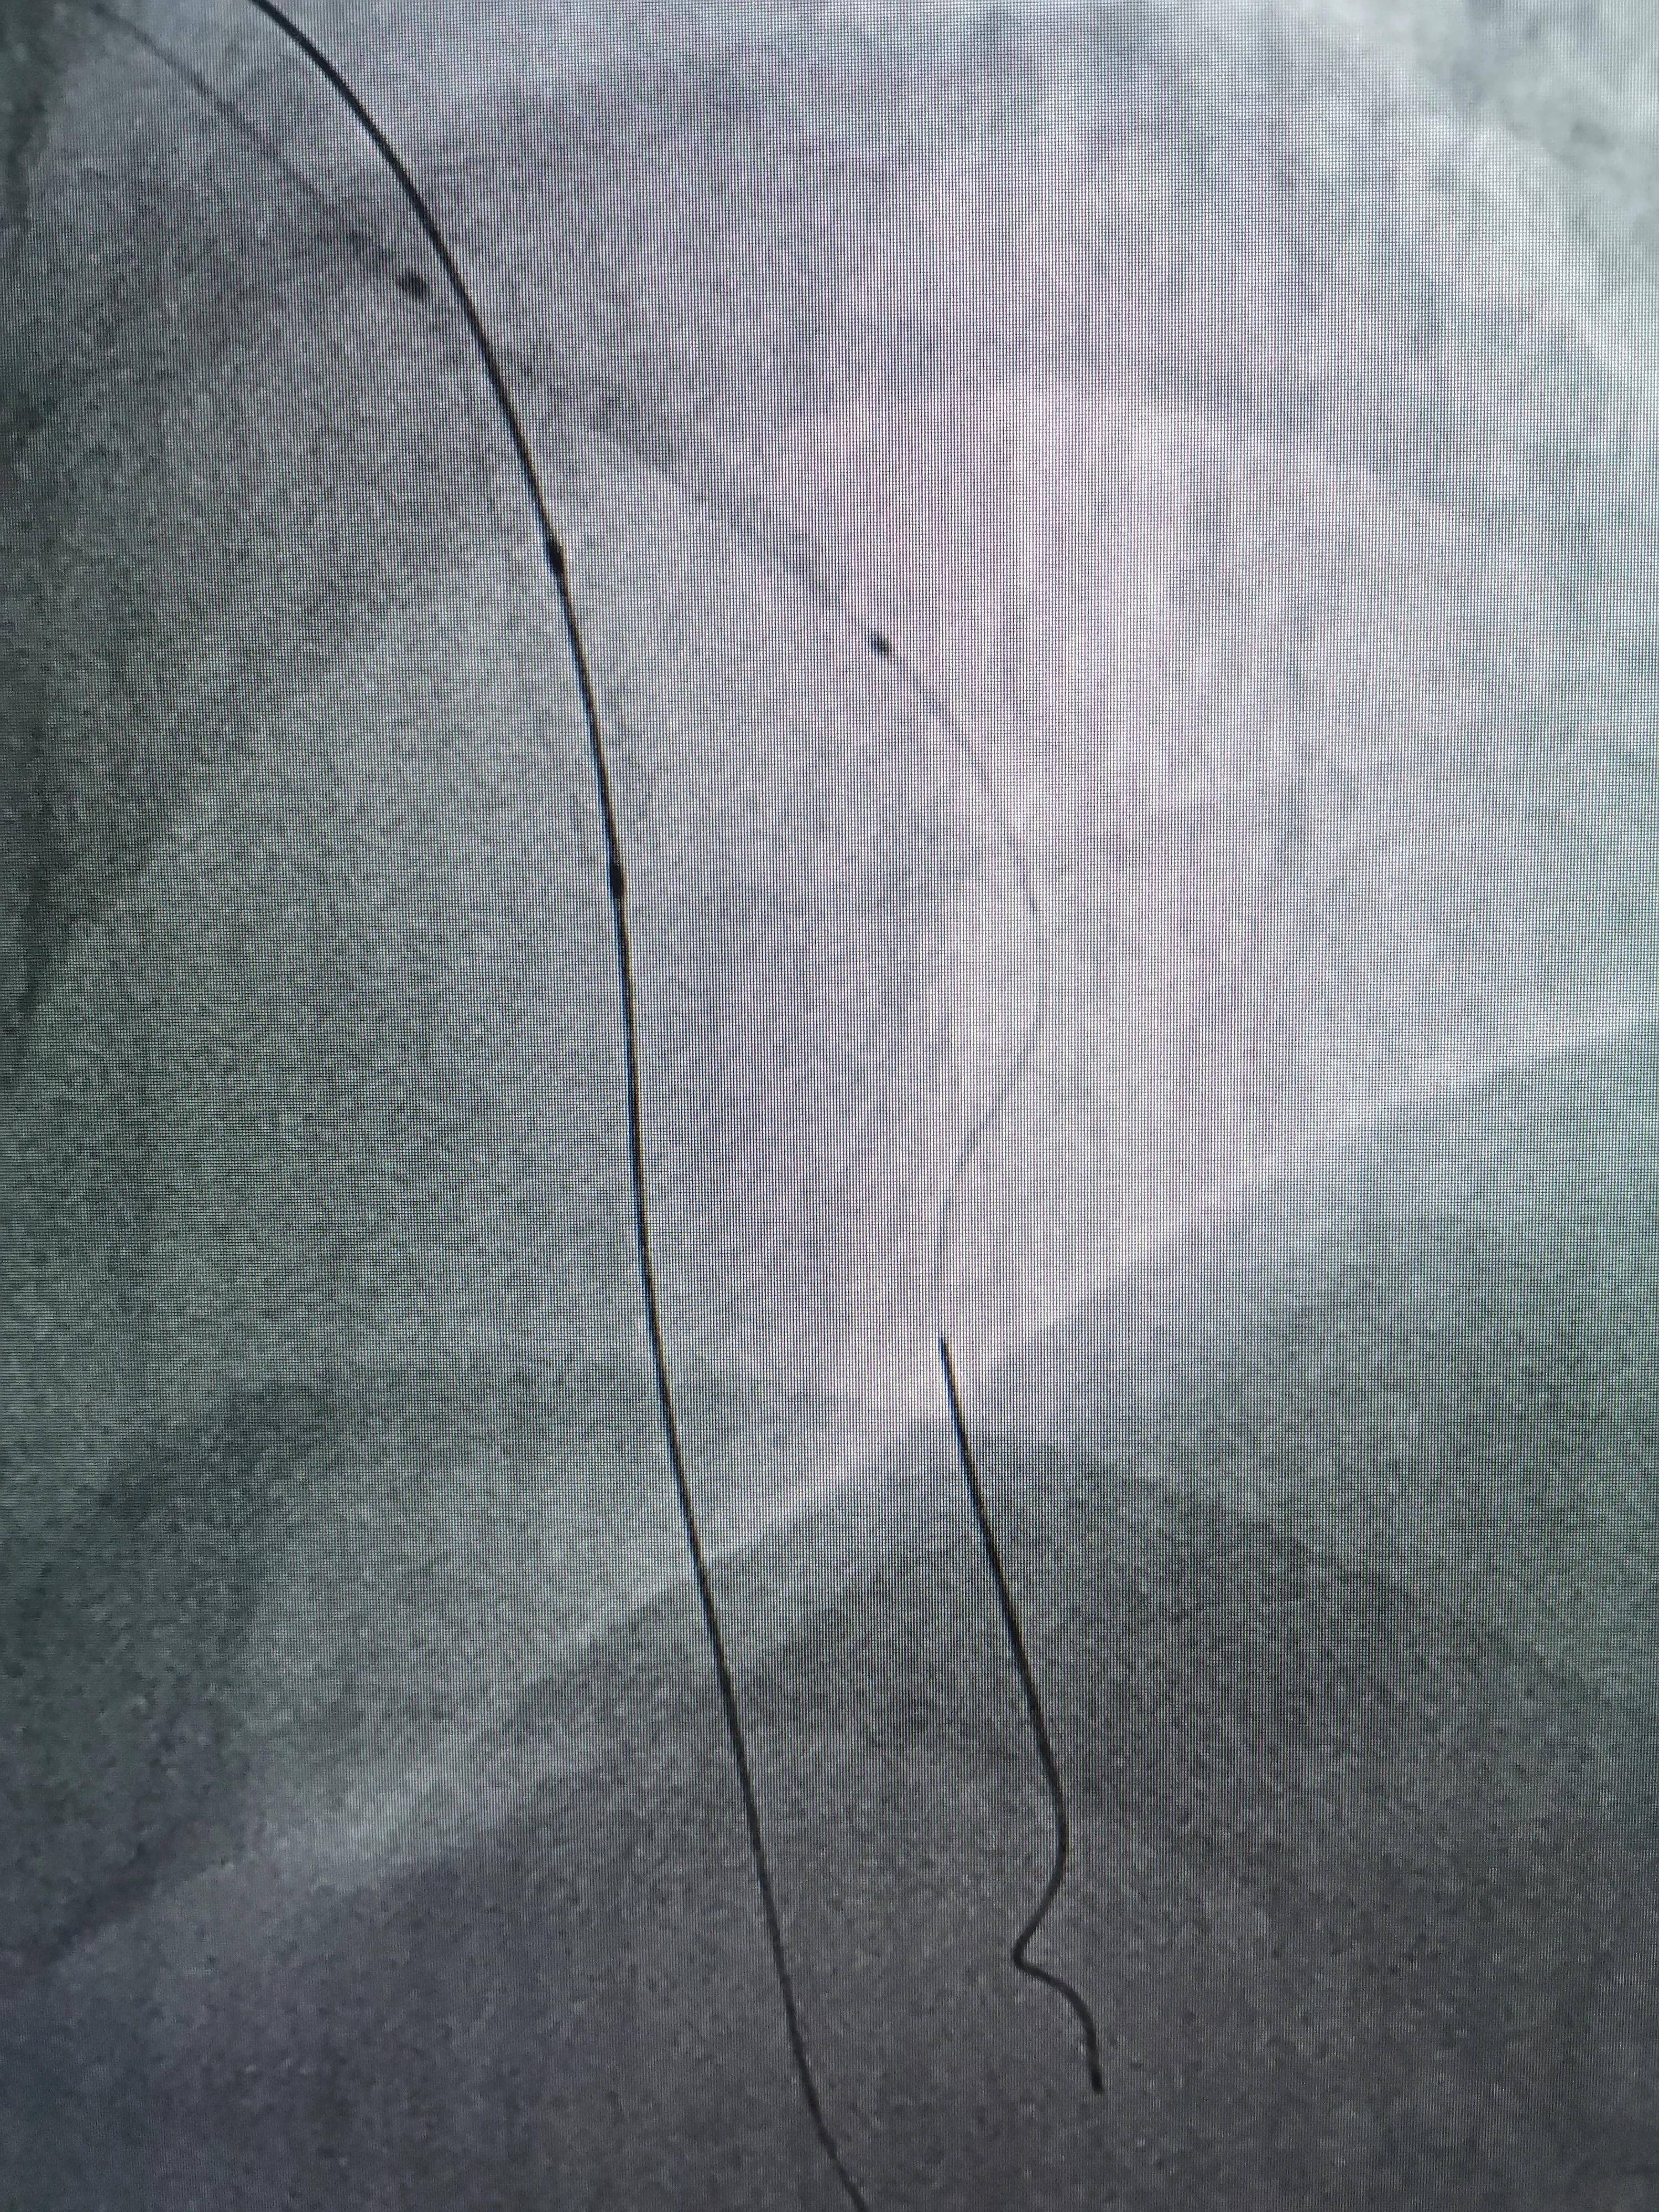

术前策略:次全闭塞病变,D1开口高度狭窄,且与主支有大于90度成角,导丝进入边支困难,先进导丝到LAD远端,扩张狭窄部位,再进导丝到D1远端保护。

(FielderXT导丝到LAD远端)

(SION导丝到D1远端保护)